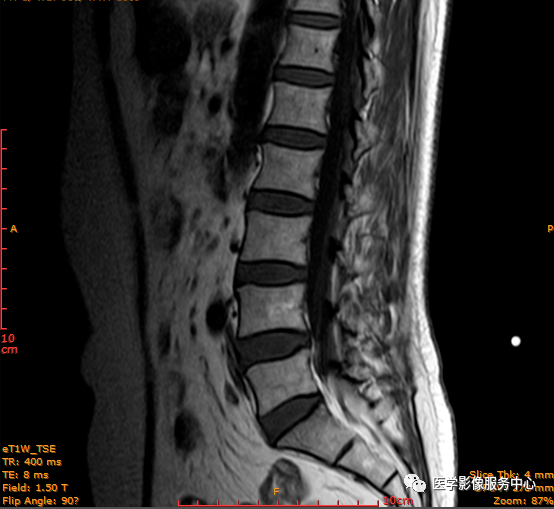

T2轴位

影像表现主要在T2矢状位及T2横断位可见椎间盘前缘或后缘可见高信号区;

日常工作因腰腿疼痛来检查腰椎MRI的很多,而腰腿疼痛并不一定就是腰椎椎间盘突出或膨出导致的,我们应该需要知道椎间盘HIZ也会引起腰腿疼痛,这种椎间盘源性的疼痛我们不能“忽略”;椎间盘后方HIZ并不少见,椎间盘后方 HIZ 在 T2WI 的局限性高信号、T1WI 呈局限性较低或等信号意味着通常所指的纤维环破裂伴随肉芽组织长入;而 T1WI、T2WI 均呈高信号可能是钙化组织。